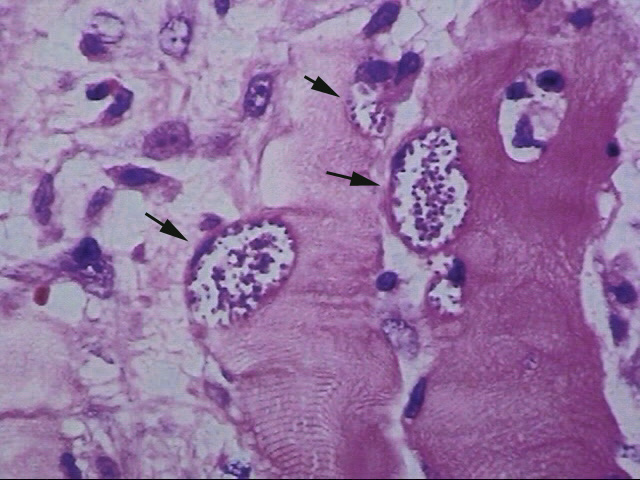

右頸部腫瘤生検組織病理所見

右頸部腫瘤の生検組織所見では, 横紋筋内にmicroorganismらしき構造物が認められた。